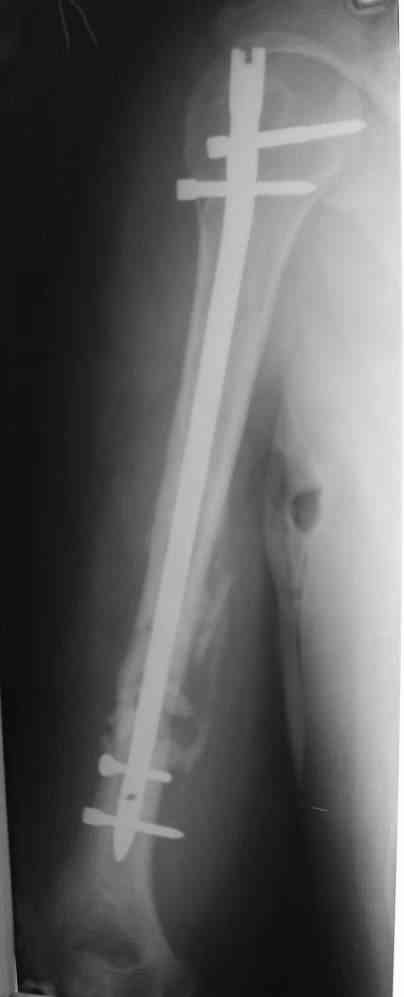

Штифт - отвисание проксимального отдела - накостный остеосинтез, нагноение, АФВ с ревизиями раны, опять пластина и снова нестабильность. Была удалена пластина и выполнен БИОС штифтом ChM (ДЕОСТ). Через 2 нед. пациент сел за руль и вышел на работу. Причем так и работает до сих пор уже 1,5 года, хотя полного сращения мы вроде бы не достигли ( снимки пришлю позже) - пациент не приходил на осмотры, общался только по телефону.

Второй пациент перенес два неудачных накостных остеосинтеза на фоне пареза лучевого нерва. Была удалена пластина и выполнен БИОС штифтом ChM (ДЕОСТ) - это была наша первая операция БИОС.